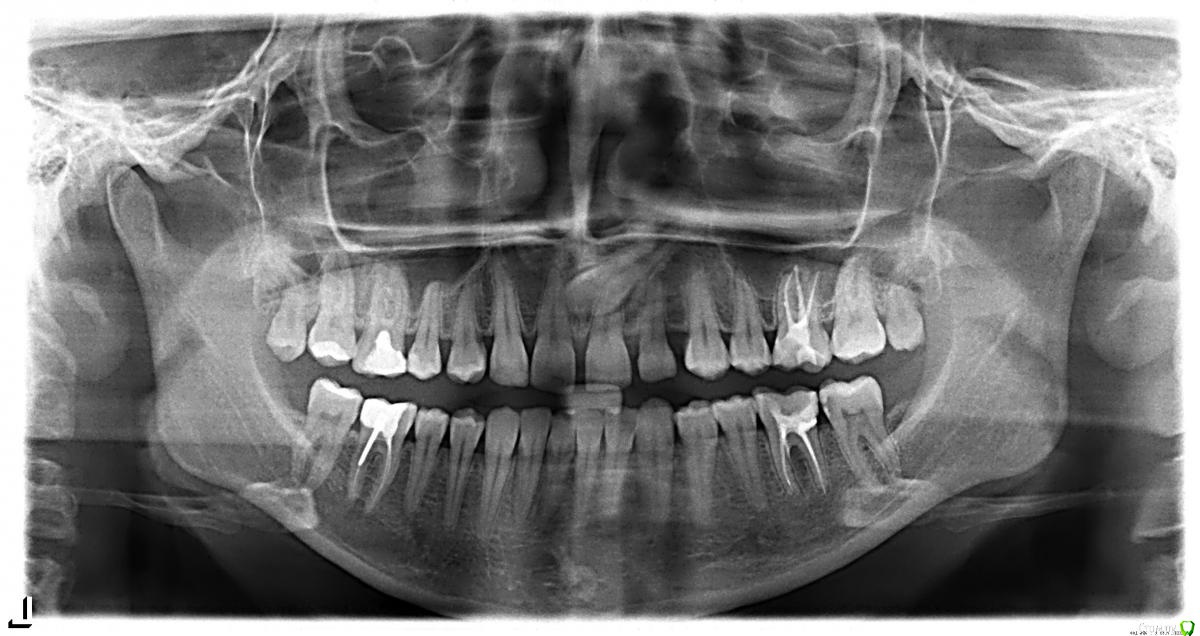

Jason Fa Опубликовано 7 апреля, 2015 Поделиться Опубликовано 7 апреля, 2015 Здравствуйте! В марте я решила ставить брекеты и сделала панорамный снимок. Выяснилось много нехорошего. Никогда не считала свои зубы проблемными, но я ошибалась. Мне 23 года. И на сегодня у меня четыре 6ки депульпированы. И у 3х из них необходимо перелечивать каналы. Плюс у меня был ретенированый клык, после удаления которого два зуба до сих пор чувствительны (1.1 и 1.2) и скорее всего их тоже нужно депульпировать и пломбировать каналы. Плюс на одной из 7ок я обнаружила кариес между стенкой 6ки и 7ки. Я прикреплю снимок и хотела бы получить комментарии врачей, так как сама не профессионал и многое на этом снимке читать не умею. Какие зубы еще с кариесом? Возможно даже под пломбами и какие еще надо перелечивать? Ссылка на комментарий

Гарриевич Опубликовано 9 апреля, 2015 Поделиться Опубликовано 9 апреля, 2015 16 и 26 зубы нужно перелечивать (это верхние 6ки)46 нужен прицельный снимок (это правая нижняя 6ка)а вот в 36 зубе возможно перфорация корняна 37 зубе со стороны 36 кариеспо поводу верхних резцов нужны как минимум внутриротовые фото 1 Ссылка на комментарий

shishok Опубликовано 7 апреля, 2015 Поделиться Опубликовано 7 апреля, 2015 Да,на 37 есть кариес на контактной поверхности. Ссылка на комментарий

Jason Fa Опубликовано 10 апреля, 2015 Автор Поделиться Опубликовано 10 апреля, 2015 16 и 26 зубы нужно перелечивать (это верхние 6ки)46 нужен прицельный снимок (это правая нижняя 6ка)а вот в 36 зубе возможно перфорация корняна 37 зубе со стороны 36 кариеспо поводу верхних резцов нужны как минимум внутриротовые фотоСпасибо! На 36 перфорация да Ссылка на комментарий